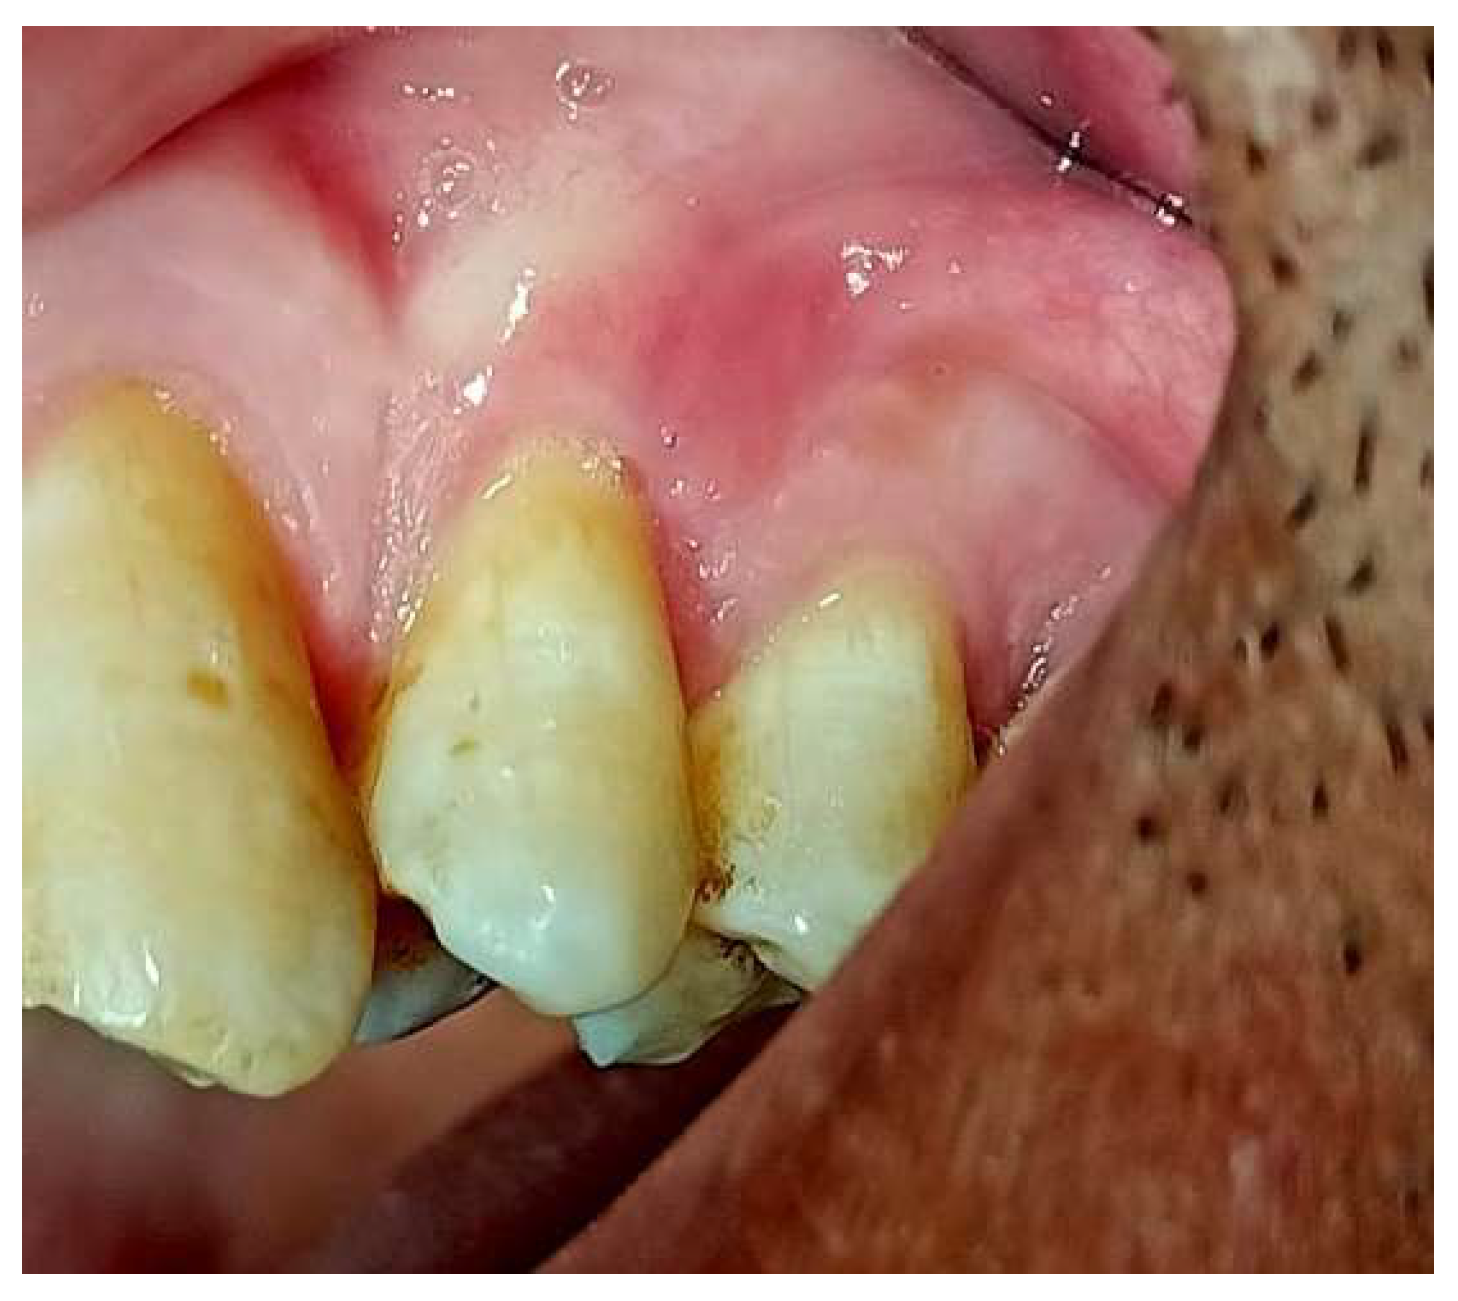

Figure 1. The case represent miller cl (lII).

Figure 2. ideal papilla and anatomical papilla coincide distally.

Case 2

45 years old male complain of sensitivity at upper lateral incisor presented at the Department of Periodontics, Faculty of Oral & Dental Medicine, with complaints of gum recession and sensitivity in the right central incisor at upper teeth. Clinical examination revealed a Miller Class III recession defect on the buccal side of tooth 11. Clinical attachment loss was recorded at 4.5 mm, and recession width at the cementoenamel junction measured 3 mm. The patient was in good general health, with no systemic diseases, medications, allergies, or smoking history.

Measuring the anatomical papillae height:

When measuring the anatomical papillae height in a rotated tooth or when papillae height is lost, it is expected that the MRC will be coincide distally with the ideal papillae and so MRC will not be parallel to CEJ.

The distance between them should equal the distance between the papillae tip and the contact point, resulting in the most coronal root area remaining uncovered with mucogingival surgery.